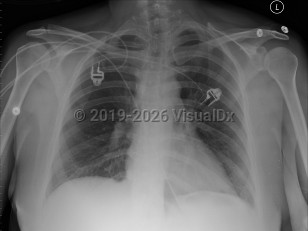

Pulmonary embolism

The clinical presentation depends upon the size, location, number and chronicity of emboli, and the patient's cardiorespiratory reserve. Often symptoms are nonspecific. Features may include dyspnea and tachypnea, chest pain (most commonly pleuritic), cough, tachycardia, arrhythmia, palpitations, hemoptysis, thigh and/or leg pain and/or swelling, pleural effusion, pulmonary infiltrates, cyanosis, syncope, and, in some cases, sudden death (classically pulseless electrical activity [PEA] arrest).